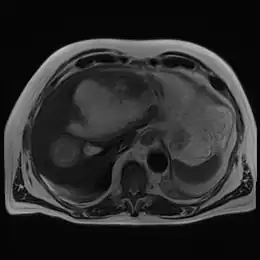

L’abcès amibien hépatique [1] est une suppuration du foie venant d'une migration d'amibes.

On peut visualiser l'abcès lors d'une échographie ou d'un scanner. On note parfois l'existence d'amibes dans les selles si l'on effectue un prélèvement.